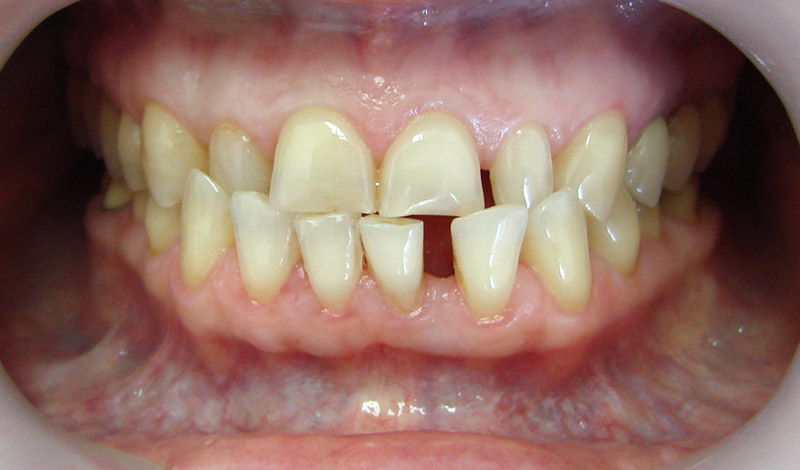

Покажу клинические случаи, чтобы было проще представить возможности ортодонтического лечения.

Начну с самого простого. Мальчик, 6 лет. Носил съемную плстинку 4 мес. В таком возрасте брекеты еще, как правило, не используют.

А это уже молодой человек 10 лет. Тоже получилось справиться без удаления. Хоть оно и было показано. Но мальчик очень упорно носил специальные аппаратики и резиночки. Покажу со всех сторон. Этот случай победил в конкурсе на конференции